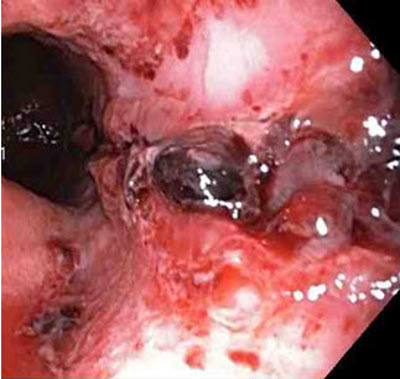

Laceração de Mallory-Weiss: a laceração com sangramento ativo aparece como um defeito longitudinal vermelho com mucosa circundante normal

Do acervo de Juan Carlos Munoz, MD, University of Florida